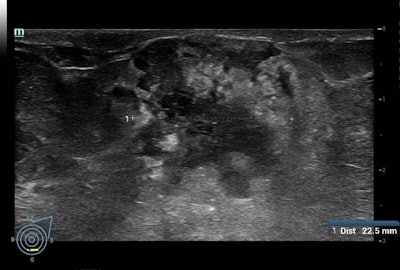

Ci-dessus: une masse BI-RADS 5 visualisée en échographie. En bas: la même masse, vascularisée en mode doppler.Par exemple, l'étude ASTOUND (dépistage adjuvant avec tomosynthèse ou échographie chez les femmes ayant des seins denses et avec une mammographie négative) a montré que l'échographie permet une meilleure détection du cancer du sein que la DBT dans les sein denses avec une mammographie normale avec un taux de rappel similaire. Cependant, selon les auteurs, la DBT a détecté plus de 50% des cancers du sein supplémentaires chez ces femmes.